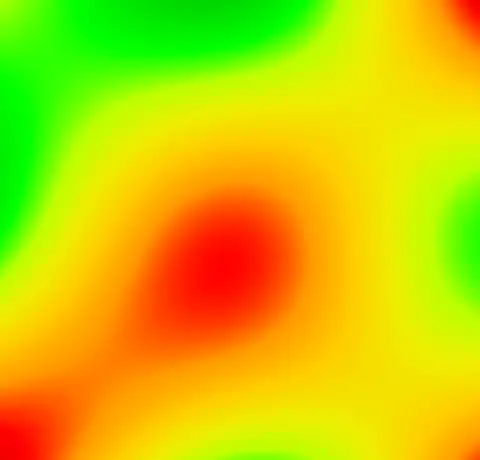

As it is very hard to pick the differences between the original and corrected version we can create a field image to visualise the differences.

imp2field -like out.mnc out.imp field.mnc

And then produce an image of it using the Spectral colormap

mincpik -scale 2 field.mnc -slice 150 -lookup -spectral field.png